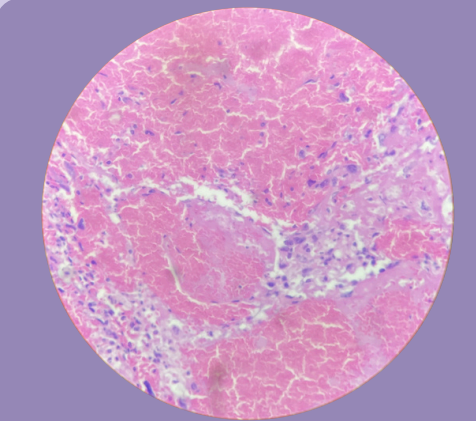

Hemangioma de hígado:

Proliferación de vasos dilatados y congestivos separados por un estroma de tejido conectivo